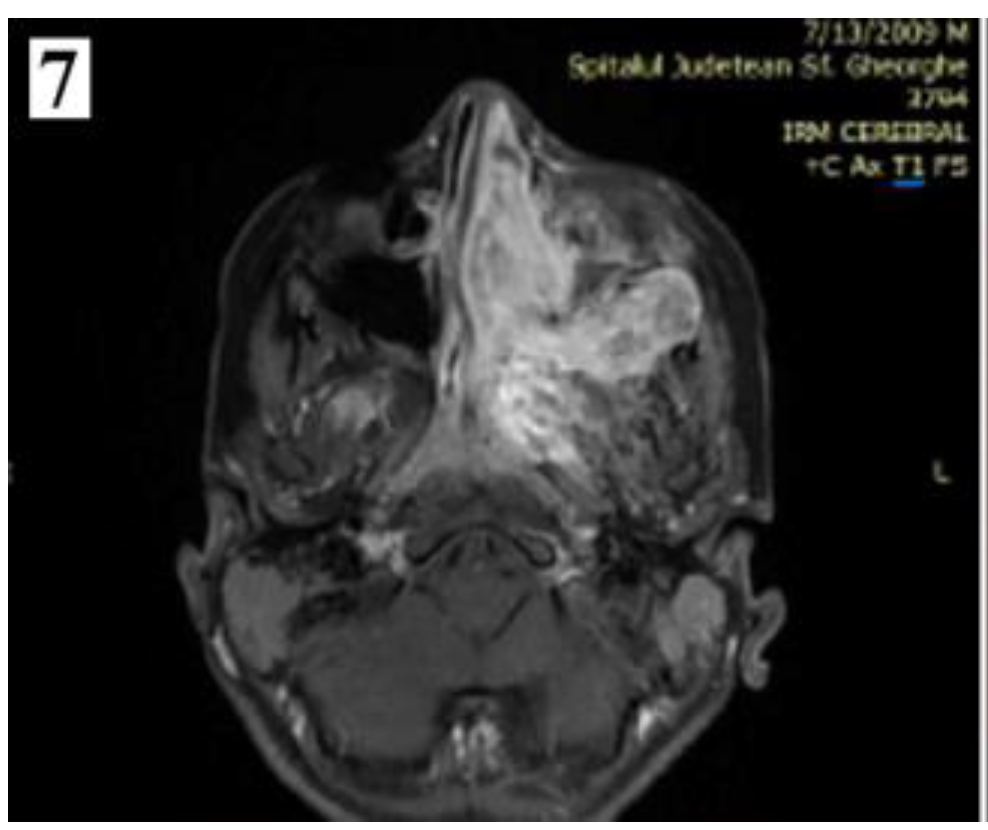

Nasal endoscopy shows a smooth, lobulated mass, pale or grey-red, intensely congestive, compressible, usually originating from behind the tail of the middle turbinate, that may occupy the entire nasal fossa and determine the obstruction of the choana.

Figure 1. Smooth, lobulated, pale or grey-red, intensely congestive, compressible mass (part 1).